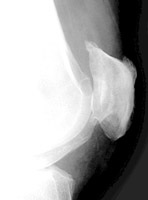

Diagnosis:Enthesopathy Discussion:Enthesopathy of the patella at the attachment of the quadriceps tendon on the axial view of the patella (sunrise view) resemble teeth. References: